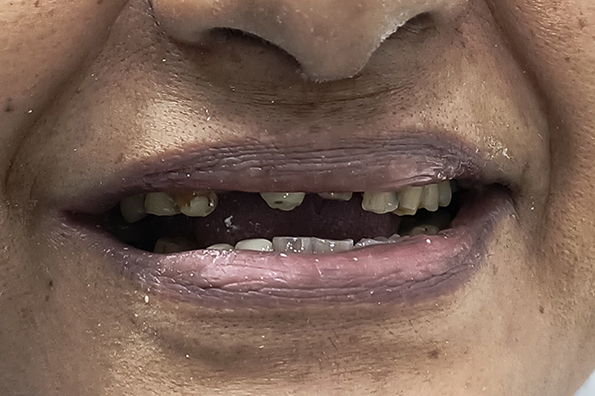

We bring strength and beauty back to your smile with advanced restorative solutions. From crowns and bridges that protect teeth to fillings that repair decay, every step is precise and comfortable. Our retreatment and post & core build-up services help preserve weakened teeth, ensuring lasting durability, comfort and confidence.

For sudden tooth pain, cracked or chipped tooth repair, or emergency extractions, our expert team is here to help. We offer same-day appointments and use modern, painless techniques for tooth extraction and wisdom teeth removal, ensuring quick relief, gentle care, and fast recovery when you need it most – because dental pain can’t wait.